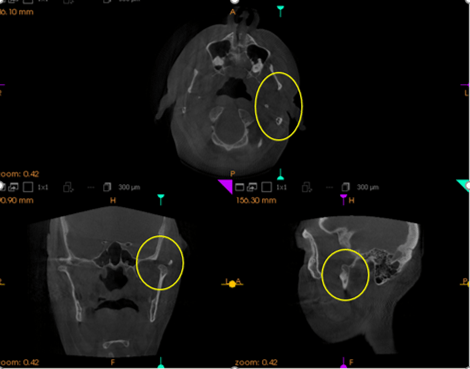

Views from the top of my head, behind my head and the left side